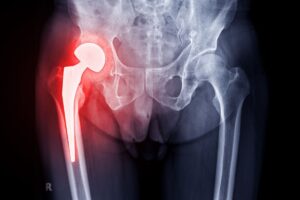

L’intervento chirurgico mira a sostituire le superfici articolari danneggiate con una protesi, una componente artificiale in lega metallica, ceramica o polietilene ad alta densità. Questo comporta un cambiamento biomeccanico significativo, a cui il paziente dovrà abituarsi in fase riabilitativa. L’organismo deve adattarsi a una nuova articolazione, recuperare il corretto schema del passo, ristabilire l’equilibrio muscolare e migliorare la stabilità del bacino.